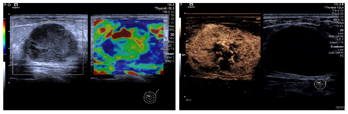

弹性成像提示:结节弹性评分为2分,质地中等;超声造影可见造影剂快速进入,病灶呈不均匀向心性高增强,局部未见造影剂进入(图2)。

乳腺纤维腺瘤的灰阶超声征象与MCB有重叠,二者时常难以鉴别。而联合多普勒超声、弹性成像及超声造影可以有效提高超声诊断的特异性。大部分MCB的血供较为丰富,Adler血流2-3级,表现为高阻力指数(RI>0.7)动脉频谱[7],与纤维腺瘤有着较为明显的区别(Adler血流0-1级,低阻力指数动脉频谱)。但多普勒超声反映的血流信号以及阻力指数与超声仪器、超声医师的操作手法有关,存在一定的主观性。而超声造影则可通过显示造影剂微泡的运动、分布,定量反映病灶区域的微循环血流灌注。髓样癌的超声造影表现为边界清晰、均匀的强化和较高的平均峰强度值,提示其存在丰富的血供[8]。此外,超声弹性成像通过反映病灶的硬度,在一定程度上有助于良恶性病灶的鉴别诊断。但既往研究发现弹性成像对MCB的鉴别存在一定争议。有研究认为MCB的弹性成像评分与纤维腺瘤无显著差异[7],而另一部分研究者则认为由于MCB周边存在纤维结构,其周边硬度较大,与纤维腺瘤有显著的差异[9]。故弹性成像在鉴别MCB中的应用仍需进一步研究。

回顾本病例,患者于洗澡时意外发现乳腺肿块,未诉特殊不适,查体时未见乳房皮肤有显著改变;病灶的灰阶超声征象与纤维腺瘤极为相似,但多普勒超声提示结节Adler血流2级(RI=0.81),超声造影呈现不均匀的向心高增强模式也进一步反映病灶丰富的血供,可与纤维腺瘤相鉴别;而MCB弹性成像提示结节质地中等,无显著的硬环征,则无法与纤维腺瘤区别。和大部分乳腺癌一样,MCB起病隐匿,临床症状不明显,易被患者忽略,以致错过治疗良机。故而应加大乳腺癌相关知识的科普,鼓励患者自查,定期体检。发现乳腺肿块后,首选超声进行筛查,辅以多普勒超声、弹性成像、超声造影可以提高诊断的特异性。此外,部分MCB血流稀少,质地中等或偏软,与良性病灶无法鉴别,为减少误诊率,必要时应行超声引导下穿刺活检以明确诊断。